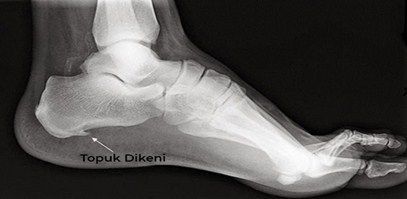

Bazı cilt sorunlarının topuk dikeni ile karıştırıldığını belirten Dr. Dinç, sözlerine şöyle devam etti: “Topuk dikeni, esasında topuk kemiğinin alt veya arka kısmında kalsiyum birikmesi sonucu ortaya çıkan kemiksi çıkıntıya denir. Kemik-kas bileşke yerinde olduğu için dışarıdan gözükmez. Halk arasında topuk bölgesinde görülen deri sertlikleri, çıkıntıları ve siğillerine de topuk dikeni deniliyor. Bunların topuk dikeni ile ilgisi olmayıp, cildiye doktoru tarafından değerlendirilmeleri ve tedavi edilmeleri gerekir. Topuk dikeni genellikle ayağın altında bulunan plantar fasya denilen kalın doku bandının iltihaplanması sonucunda ortaya çıkar. Bu doku bandı şok emici bir kemer gibi davranarak ayağı destekler. Bu banttaki stres ve gerginlik arttığında zamanla iltihaplanma gelişir ve bölgede kalsiyum birikmeye başlar. Bu birikim röntgende kolayca tespit edilebilir.”